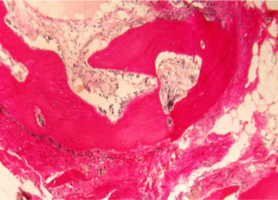

При большем увеличении (х400) на препаратах отмечается бурная пролиферация клеток соединительной ткани и макрофагально-моноцитарного ростка крови.

Тканевые макрофаги окружают фрагменты спонгиозы и осуществляют их активную резорбцию.

Клетки соединительной ткани (фибробласты) участвуют в синтезе коллагеновых волокон, и активно внедряются в поры и ячейки имплантированного материала (рис. 3).

Рис. 3. Нижняя челюсть кролика через 14 суток после остеопластики слева, смесь лиофилизированной аллоспонгиозы и ГАП 1:1.

Синими стрелками указан фрагмент аллогенной спонгиозы, подвергающийся активному лизису макрофагами (указаны черными стрелками).

Окраска - пикрофуксин по ван Гизон, х400.